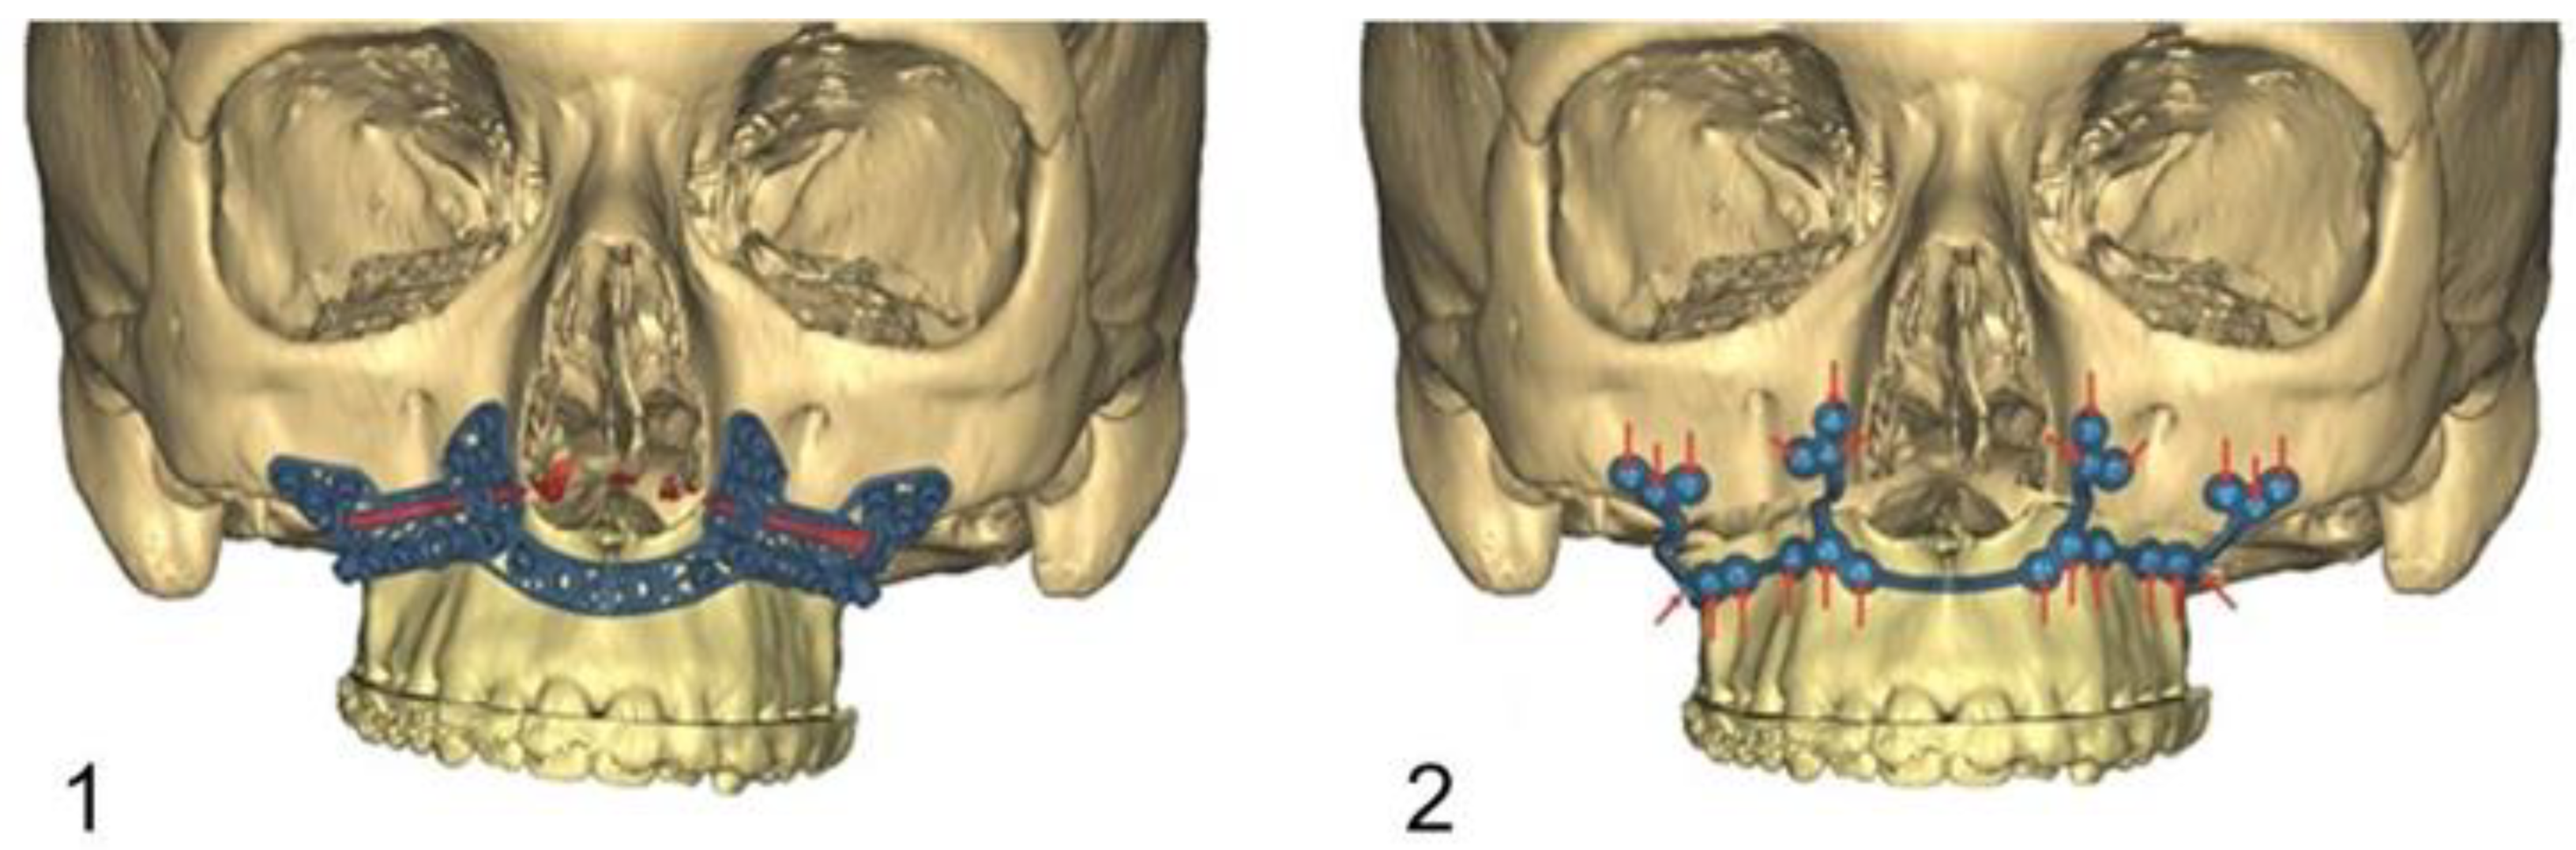

Figure 2.

Virtual computer-assisted planned drill/osteotomy guide with protection and consideration of the maxillary dental roots.

The drilling/osteotomy template and the PSI was designed and manufactured by Materialise© (Leuven, Belgium) after an online planning session with the responsible surgeon team. In the planning, the pre-drilled holes and the osteosynthesis screws were positioned in such a way that the tooth roots were spared (Figure 2). The drilling/osteotomy template is passively and temporarily fixed to the maxillary bone with two to a maximum of four additional osteosynthesis screws. The holes for the subsequent osteosynthesis are then drilled both cranially and caudally to the osteotomy using the drill/osteotomy templates preformed drill channels. The Le Fort I osteotomy line is guided in the area of the anterior and lateral walls of the maxillary sinus as virtually planned and is completed after removal of the drill/osteotomy template. After “down fracture”, the patient-specific implant is passively placed on the caudal mobile maxilla and fixed with screws through the already predrilled holes. The design and shape of the patient-specific implant encodes the final position of the maxilla in all three planes with a secure and reproducible fit (Figure 3). Therefore, the maxillary positioning can be performed intraoperatively, independently of the mobile mandible. The maxilla is moved cranially until the empty screw holes of the PSI are also passively positioned over the pre-drilled holes in the cranial part on both sides of the midface. The PSI fixation follows by using monocortical osteosynthesis screws with a diameter of 1.85 mm and a typical length of 4 mm (Figure 4).